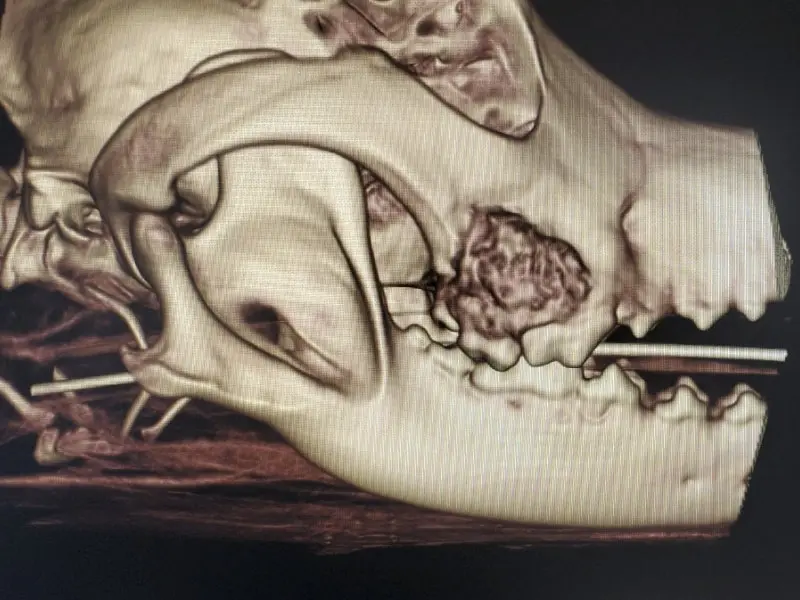

While dental radiographs are important, we are pleased to announce that we will be offering Cone Beam Computed Tomography (CBCT). Our state-of-the-art Germantown clinic has the capability to take three-dimensional images of your pet’s mouth and teeth. This will allow even more accurate diagnosis and improve patient treatment planning.